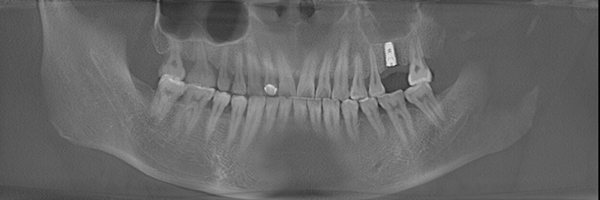

郑先生口腔内部全景片

种牙成功后的郑先生口腔ct全景